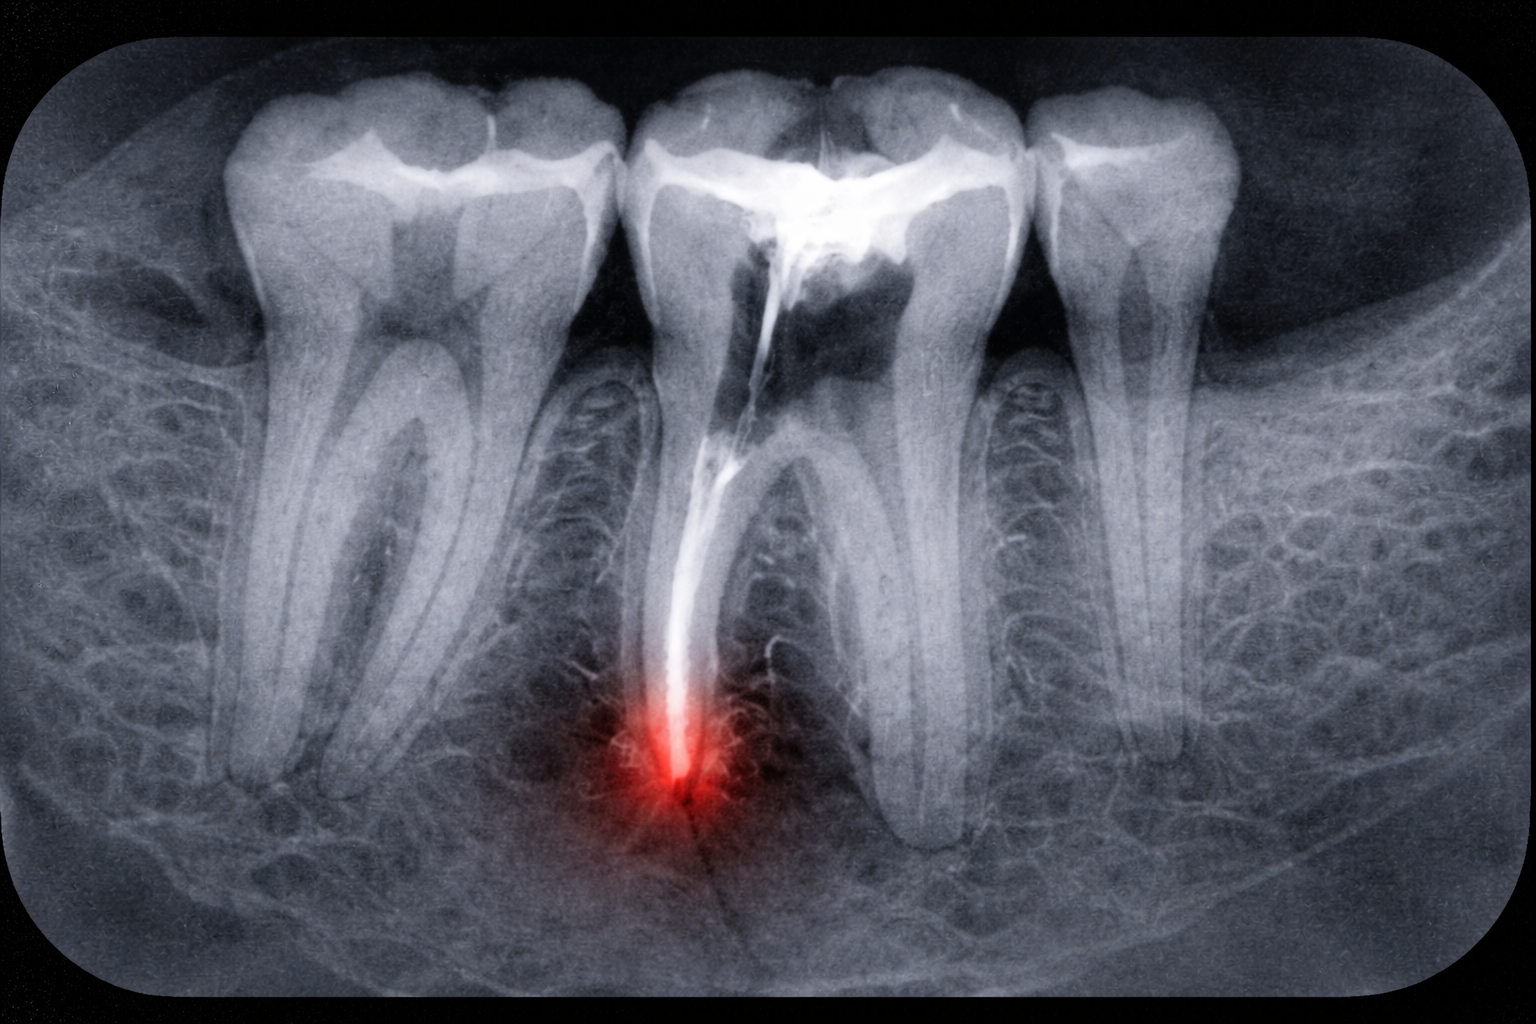

Uvnitř každého zubu se nachází tzv. zubní dřeň (pulpa) – měkká tkáň složená z nervů a cév. Pokud se bakterie dostanou až k dřeni kvůli hlubokému kazu, prasklině nebo úrazu, může dojít k zánětu nebo infekci. Endodontické ošetření dřeň odstraní, kanálky vyčistí, dezinfikuje a zaplní speciálním materiálem.

- Mikrotrauma nástroji — tenké pilníčky mohou způsobit drobné poranění tkáně kolem kořene.